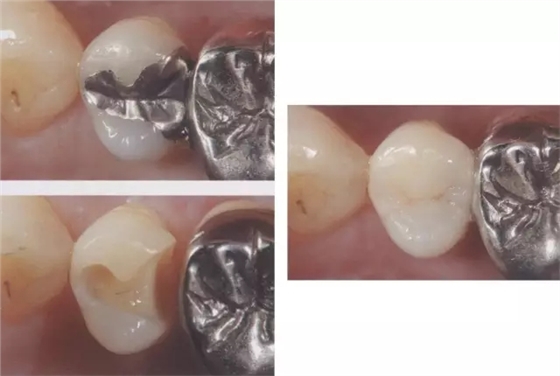

圖3 全瓷嵌體的修復(右56)。鄰接面產(chǎn)生齲齒的情況(上段,中段左),去除齲齒,并佩戴嵌體(下端)。